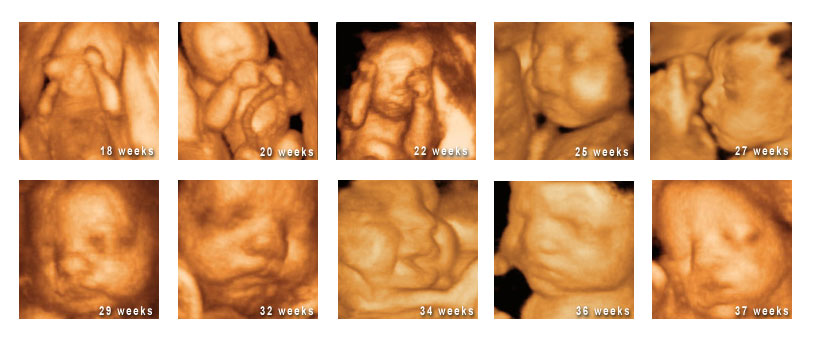

Below is depicted the later developmental stages of teh fetus between 18 and 37 weeek.